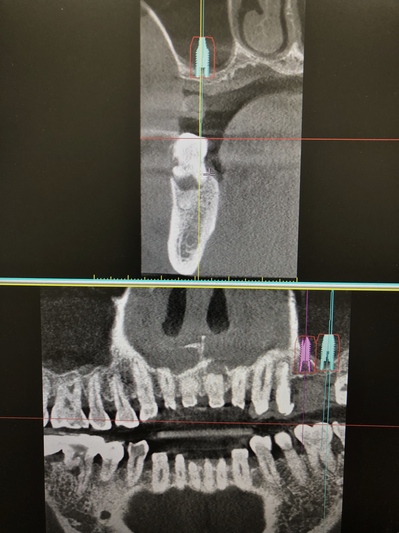

HOME > ブログ 一覧 > 左上56部へのサイナスリフトを伴うインプラント治療 2020.01.28左上56部へのサイナスリフトを伴うインプラント治療 左上56部2本欠損部へのインプラント。 術前写真。 術前CT。 インプラント治療行うには全く骨が不足している。 ラテラル法によるサイナスリフトを行い、インプラントを同時埋入。 使用インプラントはアストラEV。 間隔が狭いため、細めのインプラント2本で対応した。 術後。 骨が移植されているのが分かる。 複雑、難症例は当院の得意とするところです。 Recent Entries アライナー矯正(インビザライン、シュアスマイル)費用を2023年 1月から改訂させていただきます(01/09) 本年もよろしくお願いいたします(01/02) 年始の診療について(01/01) 新しいWEBへ移行、年末年始の診療のお知らせ(12/29) ダラダラ根管治療行っても治らないという事(12/21) Category その他の治療(126) インビザライン・矯正(52) インプラント治療(216) ホワイトニング(47) メインテナンス(21) 包括診療(95) 医院からのお知らせ(249) 審美治療(128) 日々雑感(283) 根管治療(100) 歯周病治療(90) 矯正(73) 補綴治療(45) 補綴治療カテゴリを追加(1) 診療全般(44) Archive 2023年1月(3) 2022年12月(6) 2022年11月(14) 2022年10月(6) 2022年9月(8) 2022年8月(7) 2022年7月(13) 2022年6月(8) 2022年5月(7) 2022年4月(7) 2022年3月(6) 2022年2月(7)